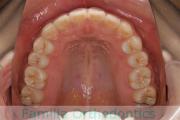

No.20V-496

- 叢生

- 年齢:

- 15歳

- 性別:

- 女性

- 抜歯部位

- 上:

- 84|58

- 下:

- 8558

全体的なでこぼこを治したいということで来院されました。上顎は右は4,左と下顎両側は5番を抜歯して、マルチブラケット法にて治療を行いました。2年強、25回程度の通院をしていただきました。

非常に強いでこぼこですので、後戻りのリスクは高めであると思われます。

- ≫治療後

-

上顎

下顎